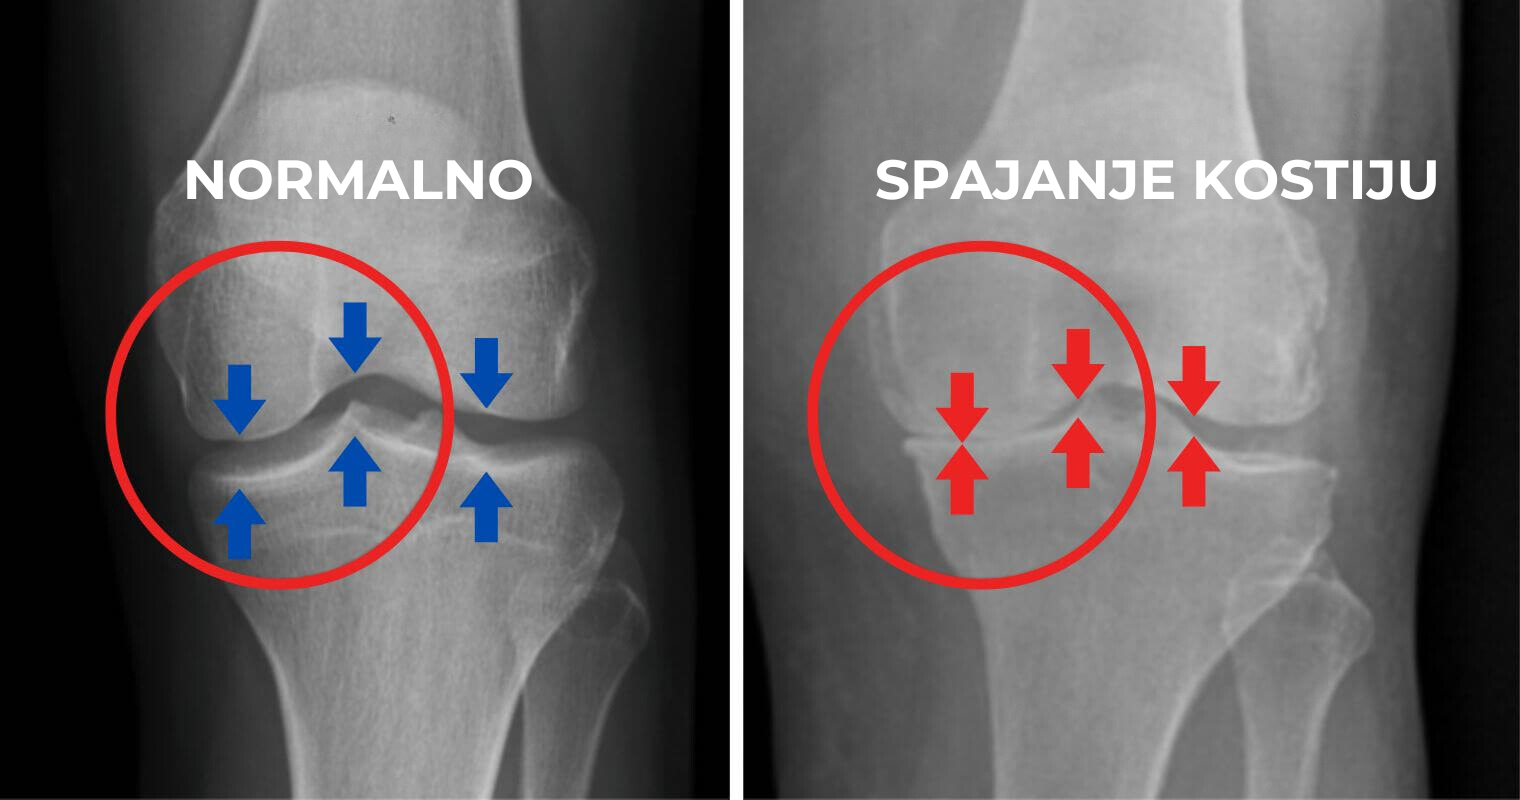

Šta ako vam kažem da su bol i ukočenost u kolenima koje osećate uzrokovani trošenjem hrskavice, što dovodi do trenja kostiju?

Kako se hrskavica vremenom troši, kosti počinju da se trljaju jedna o drugu, što uzrokuje intenzivan bol i nelagodnost. Ovo trenje dovodi do nelagodnosti, otoka i značajnog smanjenja pokretljivosti.